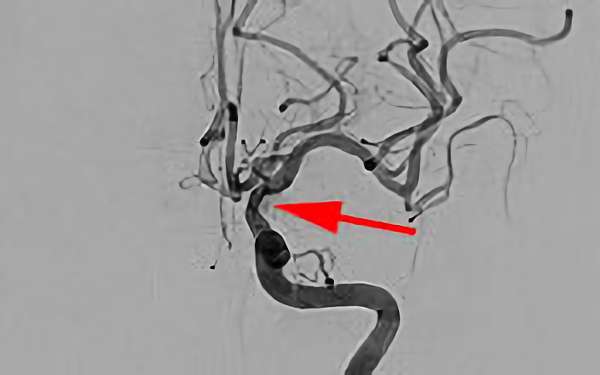

'26年4月

左後下小脳動脈瘤

80代

大阪府の病院

No.1631 手術前